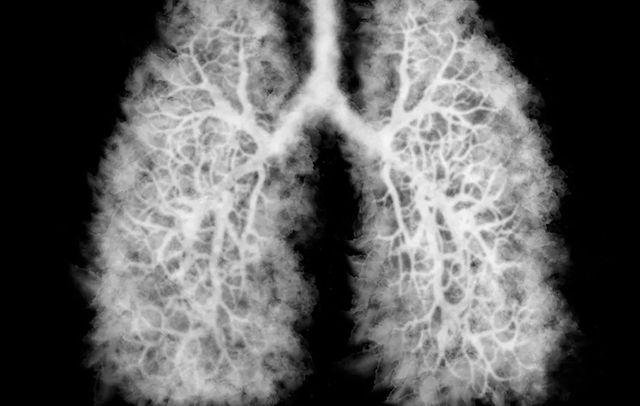

‘पॉपकॉर्न लंग्स’ को चिकित्सकीय भाषा में ब्रोंकियोलाइटिस ऑब्लिटरेन्स कहा जाता है। यह एक ऐसी स्थिति है जिसमें फेफड़ों की सबसे छोटी वायु नलिकाएं क्षतिग्रस्त हो जाती हैं, जिससे व्यक्ति को खांसी और सांस लेने में परेशानी होती है। इसका संबंध सबसे पहले माइक्रोवेव पॉपकॉर्न की खुशबू के लिए इस्तेमाल होने वाले रसायन डायसिटील से पाया गया था।

हालांकि, अब यह बीमारी ई-सिगरेट और वेपिंग फ्लेवर में प्रयुक्त रसायनों जैसे डायसिटील और एसीटाल्डिहाइड के कारण भी हो रही है।

इस रोग का मुख्य कारण डायसिटील नामक रसायन है, जो पहले पॉपकॉर्न फ्लेवरिंग में इस्तेमाल होता था, लेकिन अब कुछ ई-सिगरेट फ्लेवर में पाया जाता है।